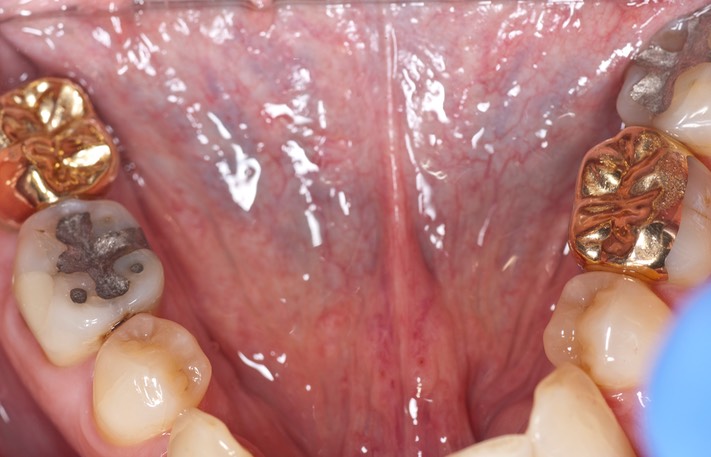

Photos of Clinical Operations

_DSC6495